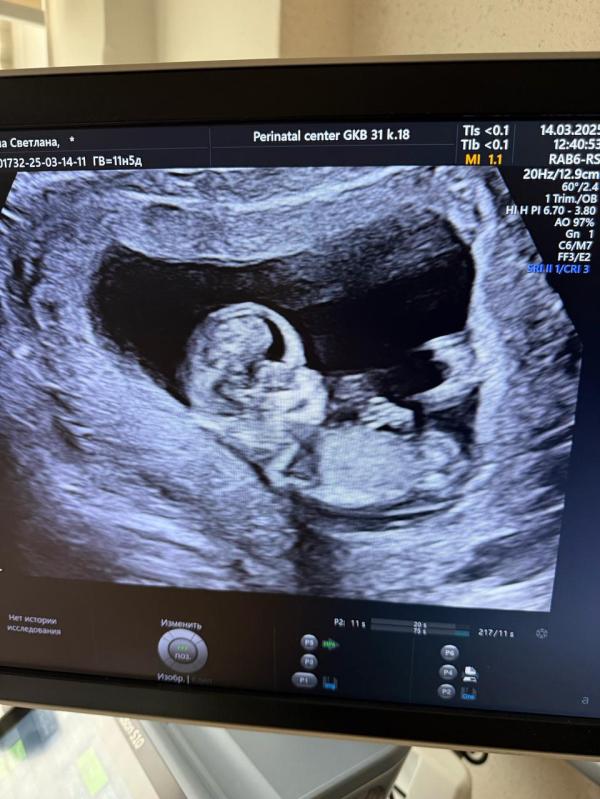

Девочки🌸 у кого есть опыт , можно предположить по фото, кого ждем? Срок по узи 12,3) врач сказала, что это не точно, но она предполагает, что мальчик🙈 третий парень🙈 я то готова, муж грустит)))

@ekaterinade, ну как знаете ) работаю уже не год и не два пренатальным диагностом) видеть можно все, что угодно) но поверьте ,иногда очевидный мальчик оказывается девочкой) на 1 скрининге. Да мы можем почти на 90 процентов озвучить пол при идеальном положении плода - но никак не потому что видим половые губы или половой член )

@gdzhst, а по каким тогда признакам озвучивается пол ??? Я конечно понимаю , что на этом сроке видно «половой бугорок» а не полностью развитые половые органы…но ведь исходя из его внешнего вида и делается предположение , не так ли?

@ekaterinade, исключительно исходя из его наклона. Который при несколько косом положении плода, либо если он слишком согнут - может быть не очень достоверным. Иногда я вижу у меня плод лежит идеально, я озвучиваю сразу что я практически уверена , но иногда бывали случаи когда кажется что мальчик , при этом я понимаю что плод лежит ну так себе) , а потом к концу исследования оказывется уже что девочка

Вот я не могу этот угол наклона рассмотреть, ни на фото, ни на видео, которое еще сняли

@brenlanda, как все пишут- фото не информативно, полностью согласна))

До 20 недели каждая 2я девочка как мальчик 😂 рано предполагать ) а фото промежность и гениталии не передает)